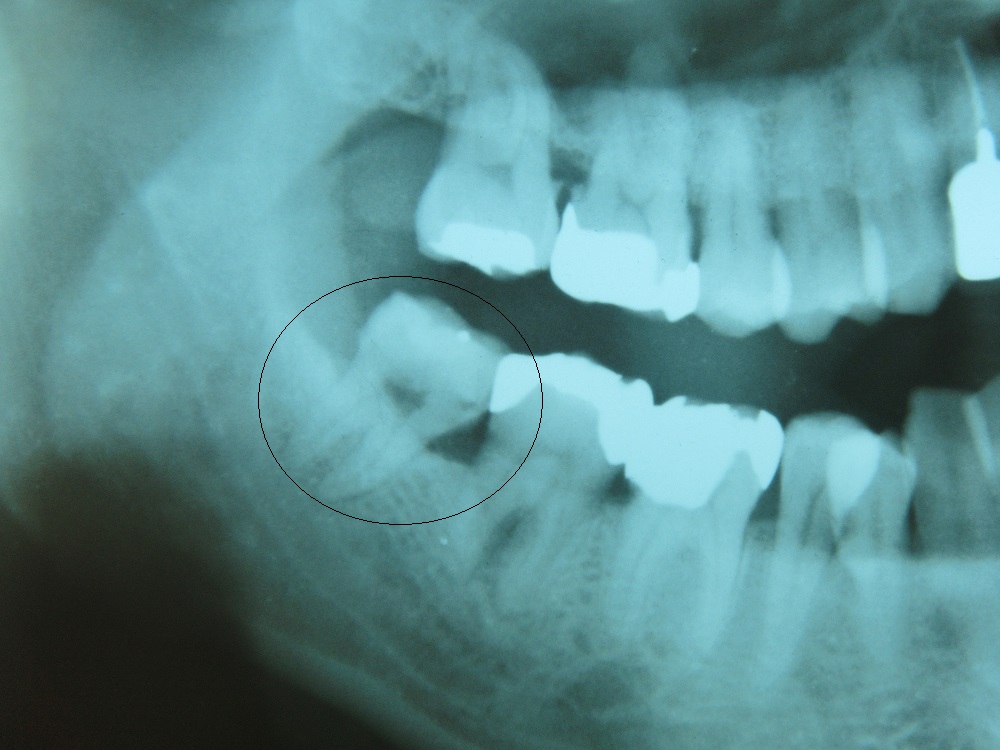

CASE2

このケースは5分くらいで抜歯します。